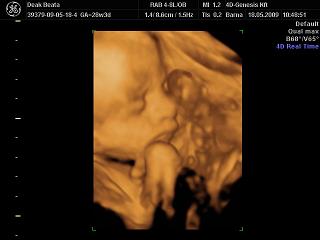

Dbea! Nagyon klasszak a fotók a bébiről, olyan édes, ahogy szopizza az ujját. Klassz a konyhabútor, szépek lesztek!